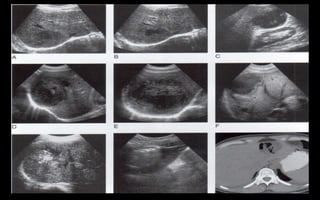

Hepatititis víricas

 El parénquima hepática

puede tener una menor

ecogenicidad difusa con un

brillo acentuado de las tríadas

postales, los maguitos

periportales

 Hepatomegalia

(agrandamiento del hígado

 Engrosamiento de la pared de

la vesícula

 La mayoría de los casos el

 Son lesiones redondas u ovales

 Ausencia de pared prominente

 Hipoecogenicidad compara con el hígado normal

 Ecos internos de bajo nivel

 Contigüidad con el diafragma

 Los abscesos amebianos son mas frecuentes en

el lóbulo derecho.

 Hay abscesos puede contener aire, por

bacterias.

Hígado graso

 Causa mas frecuente es la obesidad

 Otras causas: alcohol, hiperlipidemia mal

controlada, diabetes, el exceso de

corticoides, el embarazo, hiperalimentación

parenteral total, algunos fármacos, ente

otras

Infiltración grasa difusa

 Leve: aumento difuso mínimo de la ecogenicidad

hepática, visualización normal del diafragma y de

los vasos intrahepáticos.

 Moderada: aumento difuso moderado de la

ecogenicidad hepática; ligera pérdida de la

visualización de los vasos intrahepáticos y del

diafragma.

 Grave: aumento acentuado de la ecogenicidad;

mala penetración del segmento posterior del

lóbulo derecho del hígado y mala visualización o

ninguna de los vasos hepáticos y del diafragma